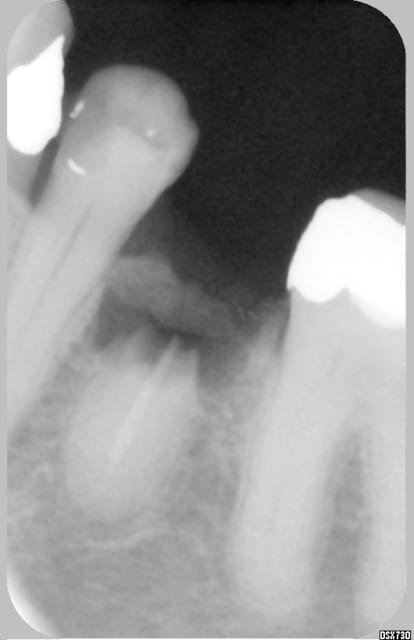

et pour celle ci qui m'a agacé 3/4 d'heure, j'ai pas l'impression que ça aurait aidé

ça me pose qd meme plusieurs problème:

pour les molaires? les apex particuliers?le temps passé? le cout de cette instrument?

et puis on dirait que l apex n'est pas entier a la sortit de l'incisive.

> et puis on dirait que l apex n'est pas entier a la

> sortit de l'incisive.

on dirait même que la racine est fracturée,elle n'est pas entière,ne manque pas que l'apex

en plus ça fait mal au coeur de voir extraire cette dent,a moins que l'indication soit une fracture il l'ont soulevée de 3 mn